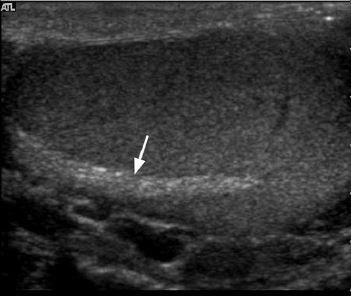

Transverse and longitudinal views of

the mediastinum of the testis